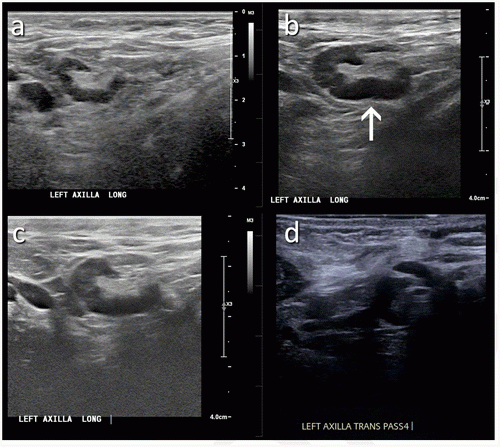

This photo gallery shows the variety of radiological presentations of COVID-19 (SARS-CoV-2) in medical imaging, including computed tomography (CT), radiograph X-rays, ultrasound, echocardiograms and magnetic resonance imaging (MRI). The radiology images show examples of typical COVID pneumonia in the lungs and the numerous complications the virus causes in the body in multiple organs, including the brain, kidneys, heart, abdomen and vascular system.

Ultrasound, especially hand-held ultrasound imaging devices, have become a primary imaging modality for novel coronavirus because of the ease to bag the device and sterilize it after use. CT and mobile X-ray systems are also used as front-line imaging systems for COVID-positive or suspected COVID patients.